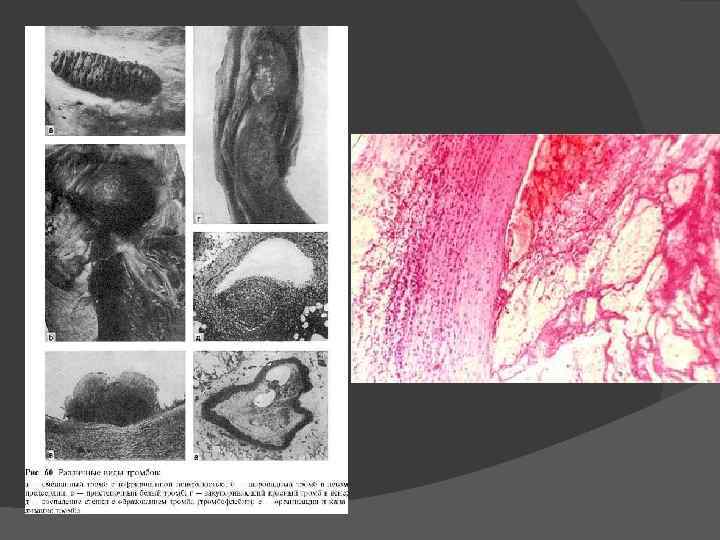

Тромбоз- прижизненное свертывание крови в просвете сосуда или полостях сердца; образующийся при этом сверток крови Факторы патогенеза: А. Местные факторы: изменения сосудистой стенки, замедление и нарушение тока крови Б. Общие факторы: нарушение баланса между свертывающей и противосвертывающей системами крови и изменения качества крови

Гиалиновый тромб

Исход тромбоза различен К благоприятным исходам относят асептический аутолиз тромба, возникающий под влиянием протеолитических ферментов лейкоцитов. Мелкие тромбы могут полностью подвергаться асептическому аутолизу. Чаще тромбы, особенно крупные, замещаются соединительной тканью. Позже выстланные эндотелием каналы превращаются в сосуды, содержащие кровь, в таких случаях говорят о васкуляризации тромба. Возможны обызвествление тромба, его петрификация, в венах при этом иногда возникают камни - флеболиты.

К неблагоприятным исходам тромбоза относят: отрыв тромба или его части и превращение в тромбоэмбол, который является источником тромбоэмболии; септическое расплавление тромба, которое возникает при попадании в тромботические массы гноеродных бактерий, что ведет к тромбобактериальной эмболии сосудов различных органов и тканей (при сепсисе).